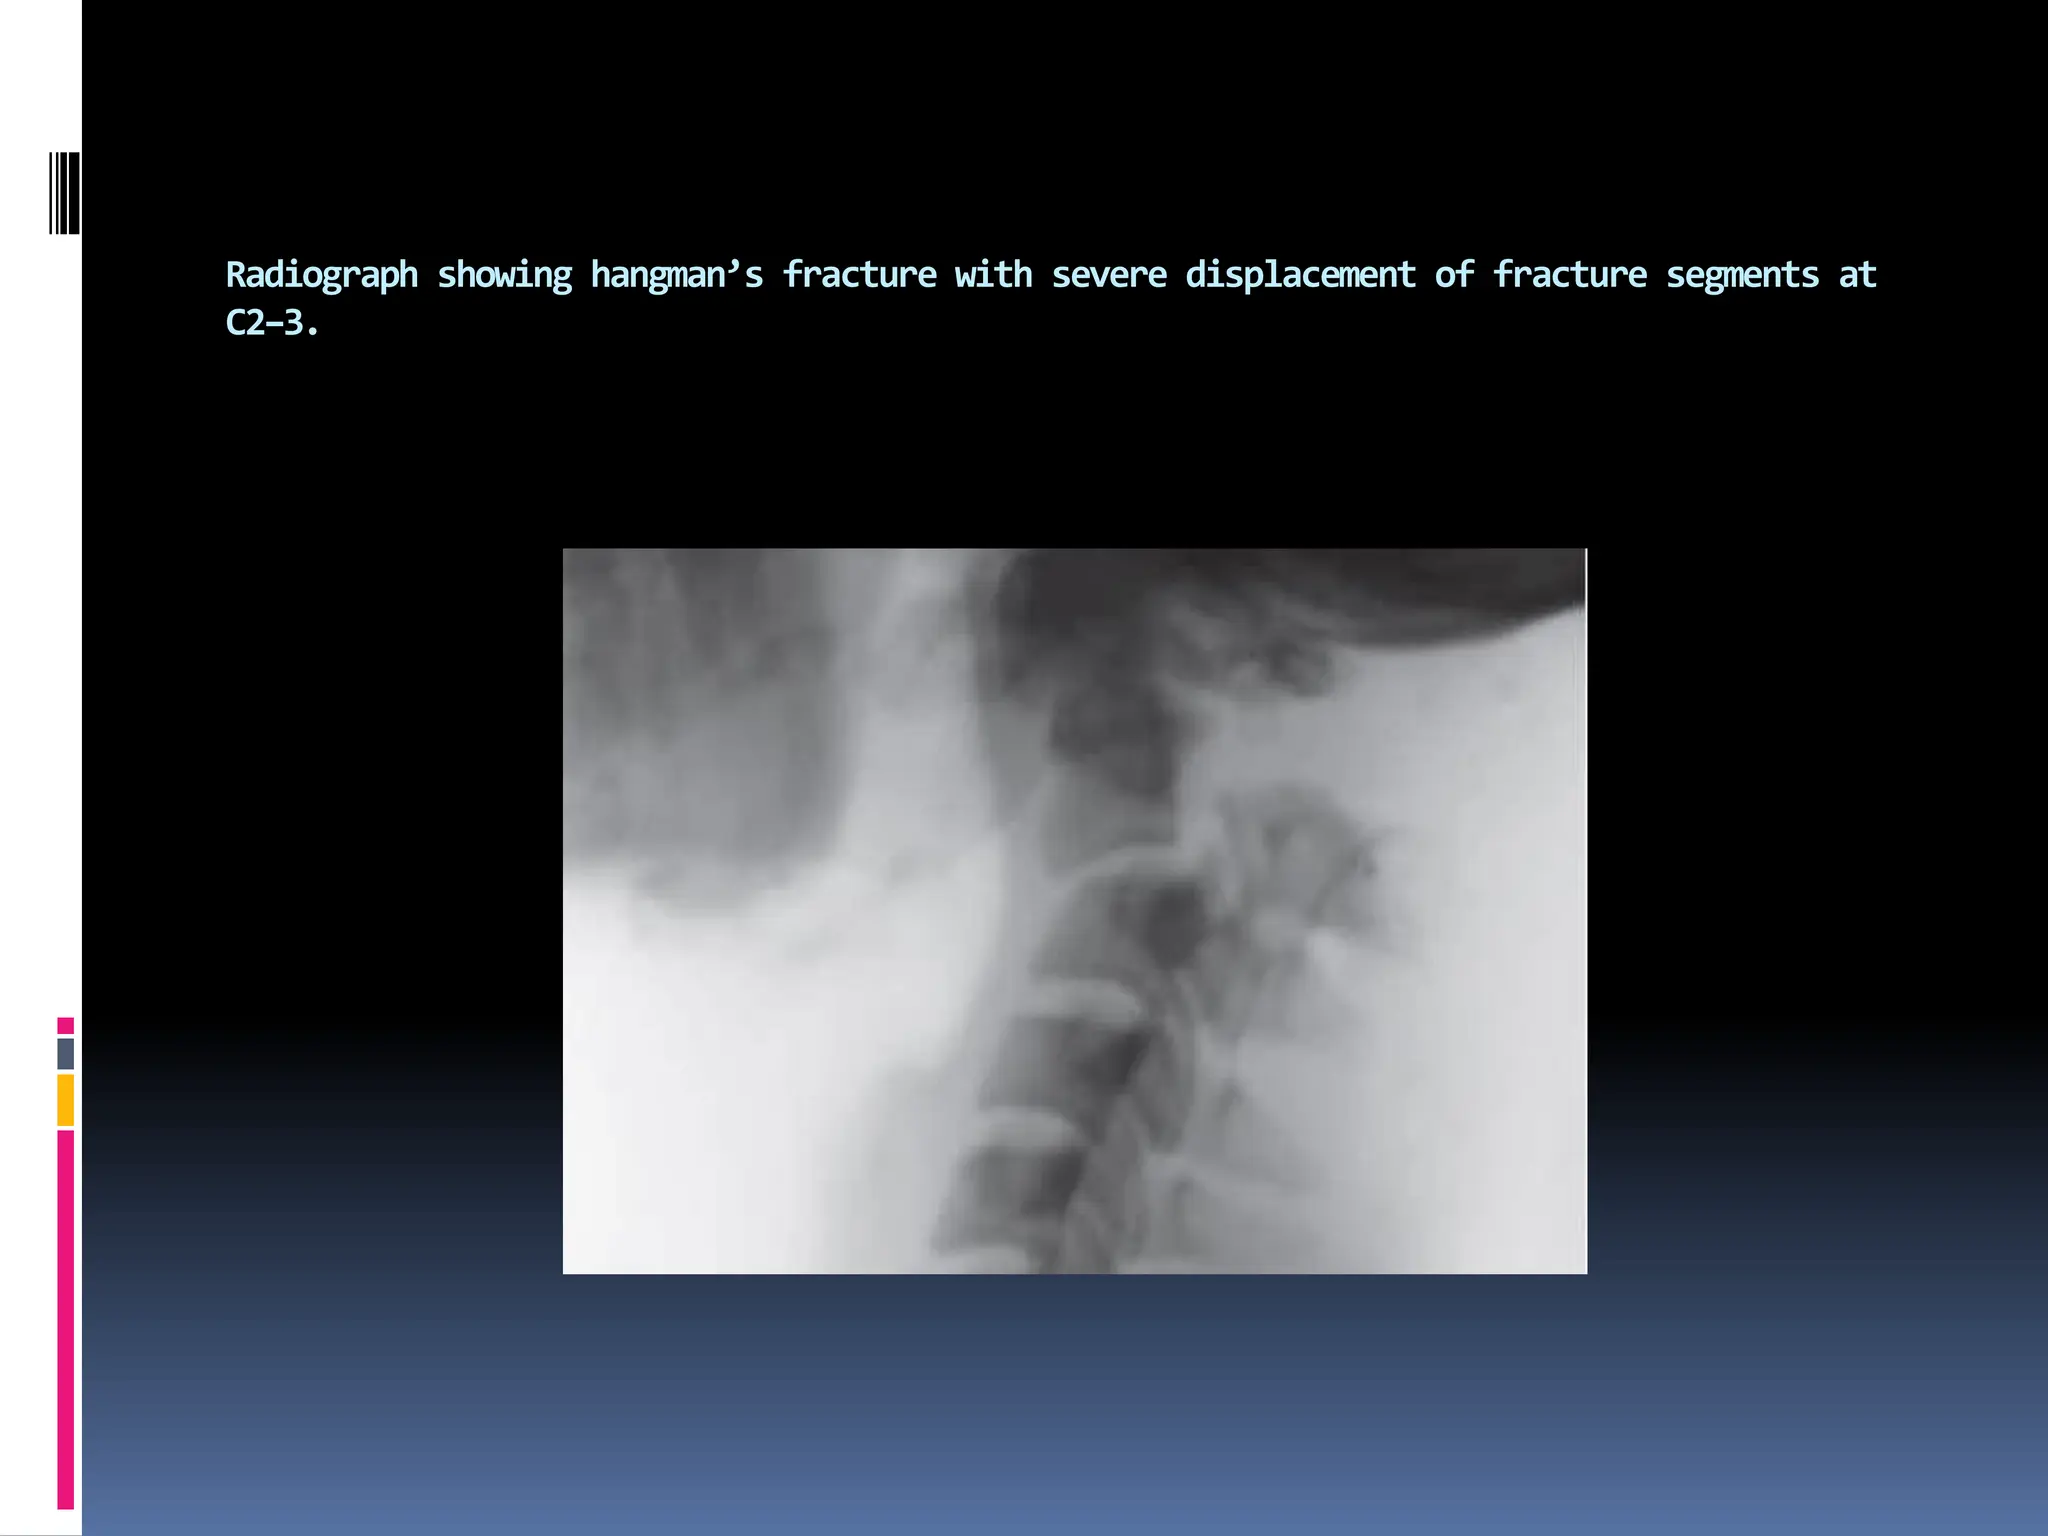

Radiograph showing hangman’s fracture with severe displacement of fracture segments at

C2–3.

The hangman’s fracture in 262 was reduced using cervical traction. This injury can heal

in a Halo external immobilization or surgical internal fixation. Note the posterior gap

between C1 and C2 due to bilateral fracture of C2 pedicles.